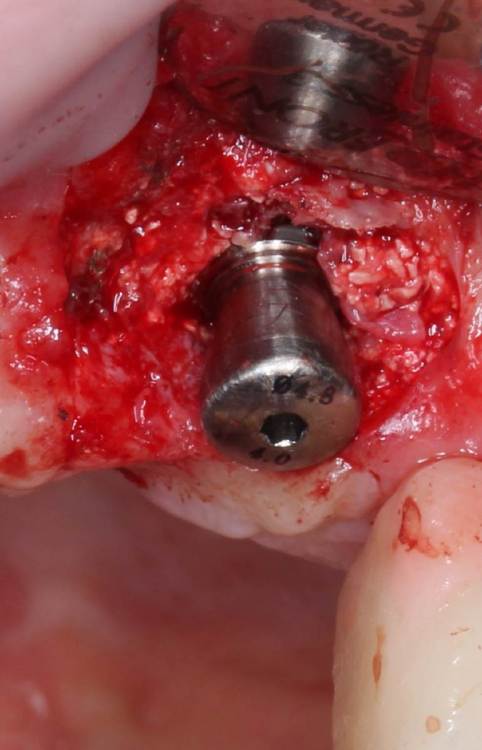

АнтонТЛТ Опубликовано 4 июня, 2021 Поделиться Опубликовано 4 июня, 2021 Жил да был имплантат 3.5мм, прижимался хорошо вместе с поджсаженной костью. Но в один момент ортопед со злобным техником решили его запротезтровать неоригинальным тибейсом в составе цирконевого моста. Имплантату это не понравилось и он решил, что ему пора на покой. И сделал себе харакири. А чтобы не сильно травмировать пациента, было решено удалить винт и имплантат. Затем сразу же поставить имплантат чуть короче и немного потолще. Время работы 50минут с учётом фотографий. 3 Ссылка на комментарий

АнтонТЛТ Опубликовано 4 июня, 2021 Автор Поделиться Опубликовано 4 июня, 2021 1 час назад, Irouil сказал: Винт, насколько я понимаю, удалялся реверсивным сверлом. А чем удалялся сам имплант? Fr-kit neobiotech 1 Ссылка на комментарий